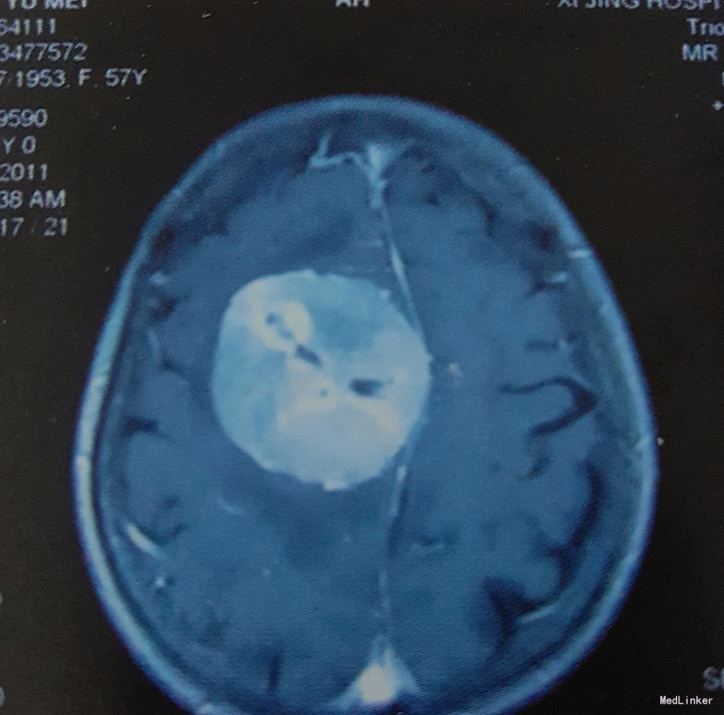

术前影像学检查:颅脑CT及MRI扫描示:右侧额顶部占位,强化效应明显,边界清,考虑脑膜瘤可能。

诊断:右额顶中央前回矢状窦旁脑膜瘤

治疗:在全麻下行开颅探查右额顶中央矢状窦旁巨大肿瘤切除术。